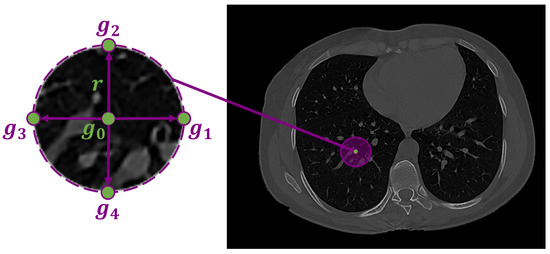

The infected region in the lung tissues is represented by the pixel-wise Gibbs energy of the proposed high-order MGRF. This Gibbs energy is computed by summing the potentials across all characteristic cliques for each pixel in the test subject. The proposed high-order MGRF model is based on using a heuristic fixed neighborhood structure (circular shape) to model the COVID-19 lung lesions. Figure 4 shows the high-order neighborhood structure with signal configurations: { B ( g 0 g 1 ) , B ( g 0 g 2 ) , B ( g 0 g 3 ) , B ( g 0 g 4 ) , N [ g 0 , g 1 , g 2 , g 3 , g 4 ] } . B denotes the binary ordinal interactions,

Figure 4. Fourth-order LBP structure, g 0 is the central pixel, g 1 , g 2 , g 3 , and g 4 are the four neighbours, and r is the radius.